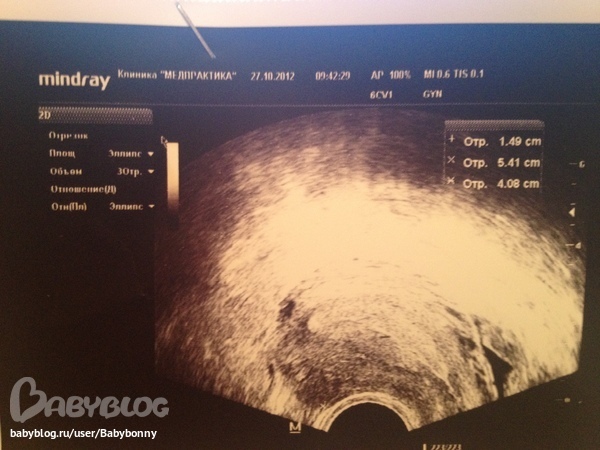

А вот, собственно фотка УЗИ мне кажется там все же есть что-то, просто мы еще маленькие.

1. матка увеличилась была 40x32 мм сейчас 54x55 мм.

2. Желтое тело соответствует нормк d=12 мм.

3. Эндометрий тоже вроде бы нормальный для беременности - 15 мм.